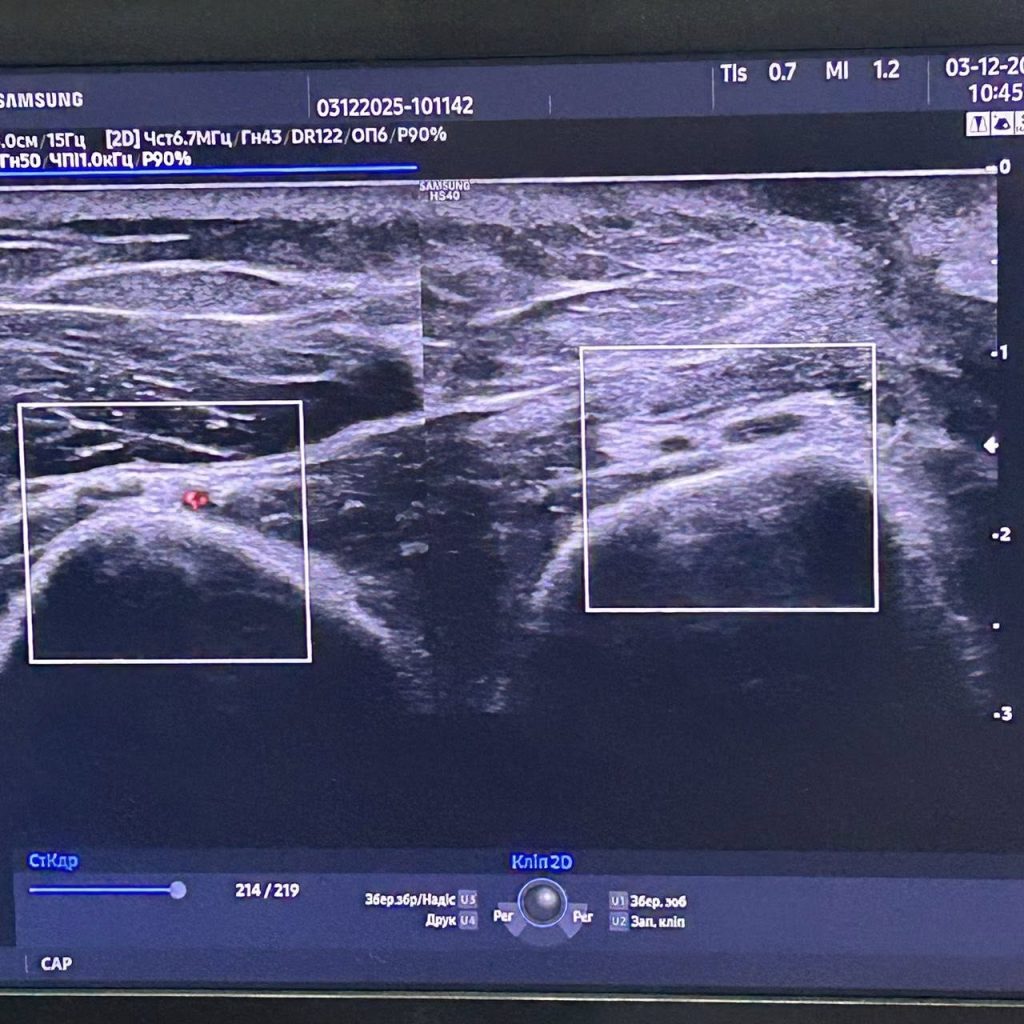

Надзвичайно продуктивний день! У вас так буває, коли нібито і натомилась, і одночасно настрій хороший? Мабуть тому, що ми почали ранок з навчання. З нами ділилась своїм досвідом неймовірна жінка, експерт в галузі УЗ діагностики пані Людмила Осадча. В пошуках нервів верхньої кінцівки ми провели чудовий ранок! Навчайтесь, Друзі!